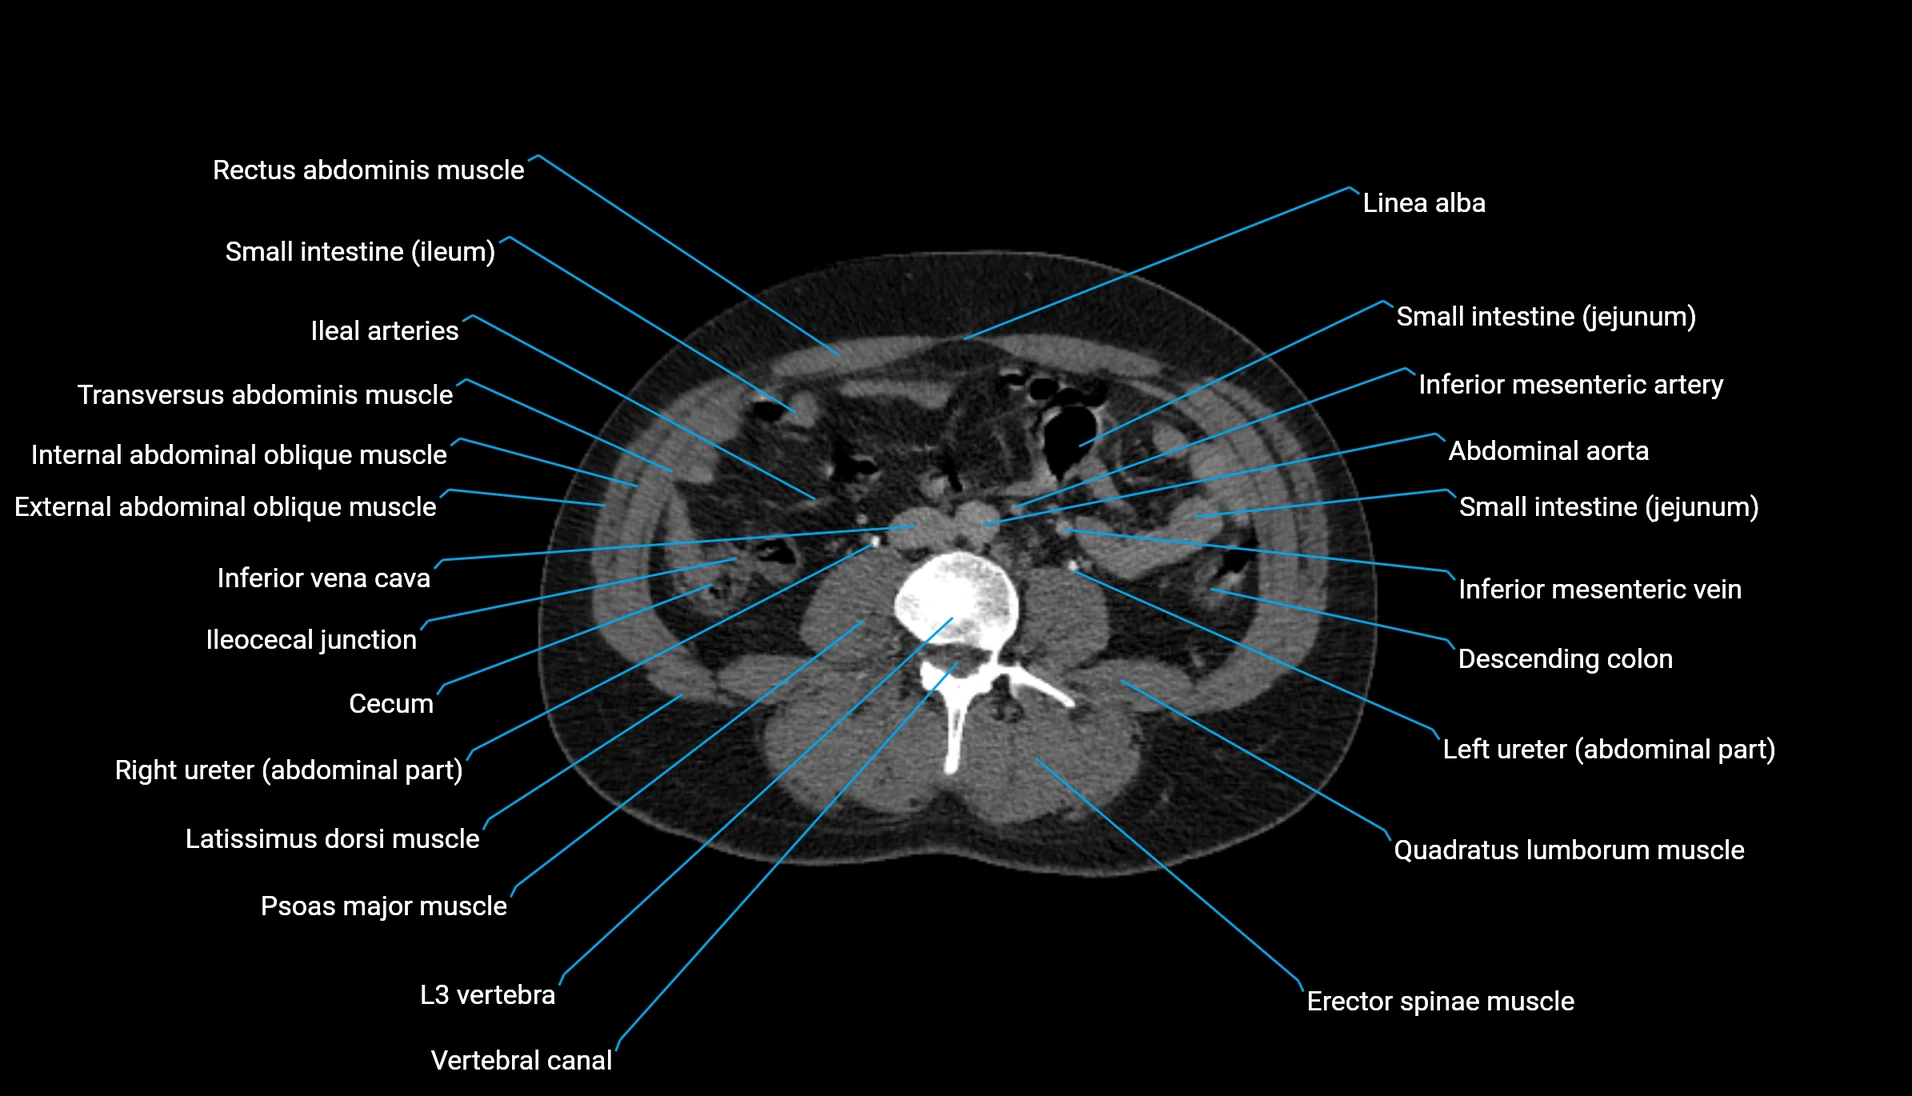

CT Appearance

Non-contrast CT:

-

Demonstrates cortical bone of acetabular rim in excellent detail

Detects fractures, dysplasia, retroversion, or bony overcoverage (pincer impingement)

3D reconstructions used in preoperative hip surgery planning

CT VRT 3D image

CT image